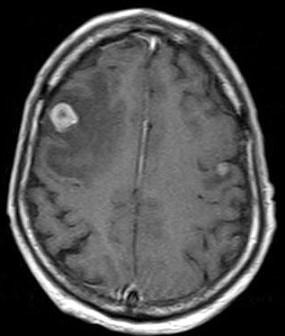

问题 男,77岁,胃癌术后2年,头痛1月,请结合影像图像选择最可能的诊断()

选项 A.脑脓肿 B.松果体瘤 C.神经胶质瘤 D.胃癌脑转移 E.脑膜炎

答案 D